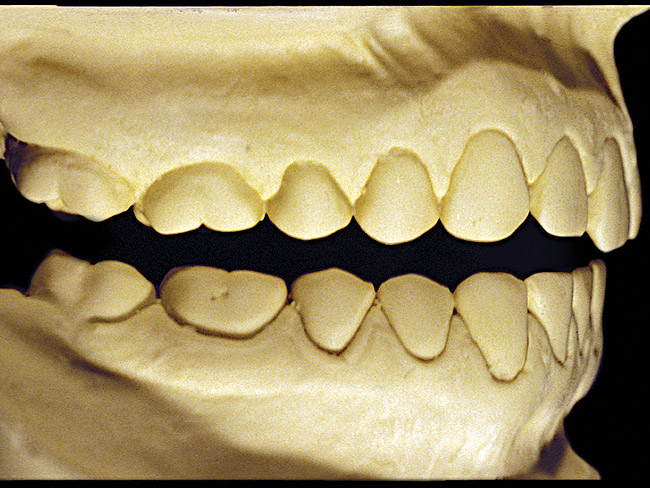

Figure 9  Moderate NCLTS from toothpaste, right facial view.

Figure 9

Figure 10  Moderate NCLTS from toothpaste, left facial view.

Figure 10

Figure 7 and Figure 8 are examples of NCLTS resulting from toothpaste. Upon examination, one could see that the overall anatomical detail of the teeth was faded with a sandblasted appearance. A closer view of the facial surfaces (Figure 9 and Figure 10) illustrates this to a greater degree and one can observe that the normal intricate facial anatomy was completely missing. It is interesting to note there was no cervical recession of the gingiva, even though every surface of every tooth had been abraded. This is due to the fact that this patient had always used a soft, round-ended filament toothbrush.21-22 This patient's sole desire regarding her oral hygiene was to get her teeth whiter.

So that the previous example is not misleading, the behavioral profile of the toothpaste abuser is not necessarily the "caries-free immaculate oral hygiene patient," but can be virtually anyone who brushes their teeth with toothpaste. Figure 11 and Figure 12 illustrate a more advanced example of toothpaste abuse showing a patient with multiple restorations and some unkempt teeth. The anatomical details were faded with a sandblasted appearance and the silver alloy restorations were highly polished. The facial surfaces of the mandibular canines and premolars were affected the most, creating the pathognomonic pattern. Figure 13 and Figure 14 are a close-up view of this area, illustrating a cupping or cratering effect, but of the asymmetrical variety. This patient did not like the color of his teeth and spent an inordinate amount of time brushing his teeth. Again, likewise due to the exclusive use of a round-ended, soft-bristle toothbrush, note there was no cervical gingival recession in this case either. When the featured casts illustrating toothpaste abuse (Figure 7, Figure 8, Figure 9, Figure 10, Figure 11, Figure 12, Figure 13 and Figure 14) were hand-articulated, the worn surfaces did not match up and the diagnosis of toothpaste abuse was confirmed.